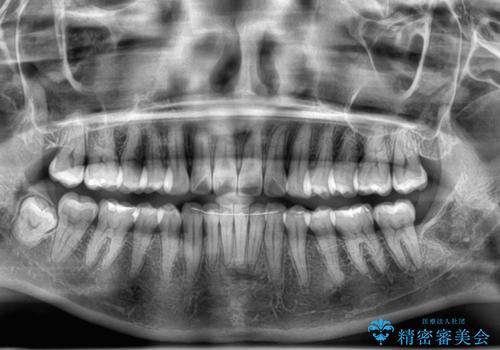

- 上下前歯の叢生を気にして来院された患者様です。

軽度な叢生であり、安価で短期間の治療を規模されていたため、インビザライン・モデレートを用いて矯正治療を行うこととしました。